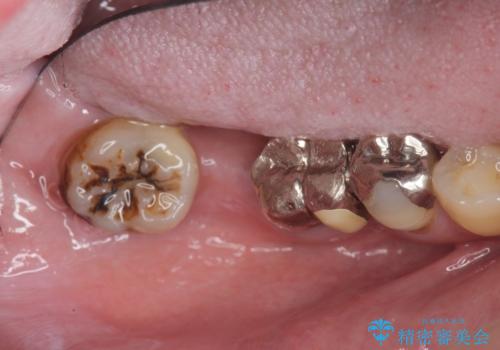

- 銀歯だらけの口腔内で将来歯がなくなるのではないかと不安になり、精査、治療を求めて来院されました。

歯周病や虫歯・強度の問題がありながらも無理やり残していた長期的な予後の見込めない歯を抜去し、インプラントを用いてしっかりと噛めるような口腔内環境の確立を目指します。